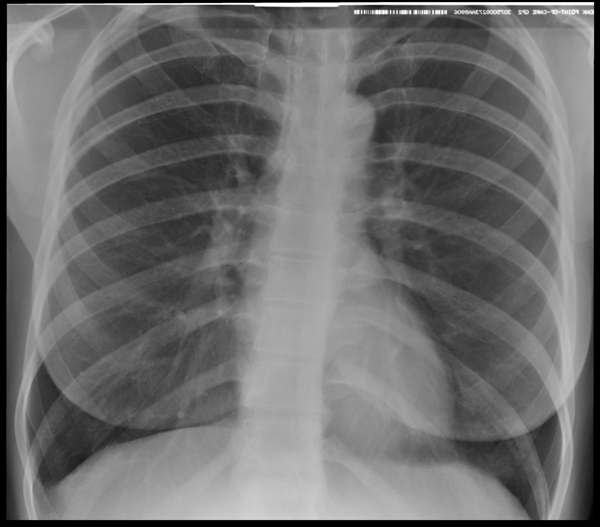

Наиболее частой причиной, по которой врачи различных специальностей, в первую очередь врачи терапевты поликлиник, назначают рентген легких, является подозрение на пневмонию.

Пневмония – простыми словами воспаление легких – острое воспаление легочной ткани инфекционного происхождения с преимущественным поражением альвеол и интерстициальной ткани легкого. При этом жидкость скапливается в просвете альвеол, что ведет к уменьшению дыхательной поверхности легких. Пневмония может быть самостоятельным заболеванием или быть осложнением другого. Заподозрить пневмонию можно при аускультации (выслушивании) легких при дыхании. Поздняя диагностика и задержка с началом антибактериальной терапии ухудшают прогноз заболевания, возможен летальный исход. Поэтому при малейших подозрениях необходимо сделать рентген легких, особенно пожилым пациентам, а при подтверждении диагноза – поставить вопрос об экстренной госпитализации. Пневмония может лечиться и дома, но такое решение может принять только врач, основываясь на оценке состояния больного, рентгенологической картины легкого и анализов крови. Лечение пневмонии в большинстве случаев требует внутривенного введения антибиотиков, инфузионной терапии (капельниц) и других препаратов. Пациенты, обратившиеся в медицинский центр «Ваше Здоровье», смогут получить весь комплекс необходимых лечебно-диагностических мероприятий, в т.ч. рентген на дому.